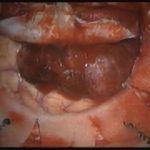

術中写真

摘出 後